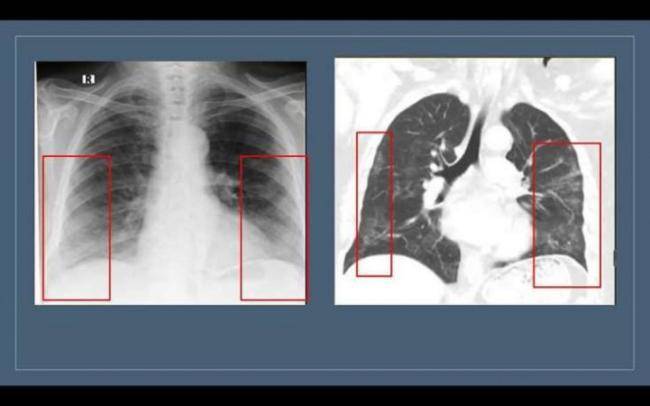

“Buzlu şüşə” görüntüsü döş qəfəsinin rentgenoqrafiya və KT müayinələrində aşkar edilir. Lakin bu məsələdə rentgenoqrafiya müayinəsinin həssaslığı aşağıdır. Ona görə də yoluxmanın ilk 1-4 günlərində rentgenoqram 25% hallarda tam normal ola bilər. Bu, pnevmoniyanın olmaması demək deyil. “Buzlu şüşə”nin KT müayinəsində görülməsi daha spesifikdir", həkim bildirib.

Bu o deməkdir ki, normalda şəffaf havalı görünən ağciyərdə belə hallarda yarımşəffaf zonalar izlənilir, ağciyər sanki dumanlı görünür. Bu zaman bronx strukturlarının və pulmonar damarların saxlanması ilə ağciyərlərin eksudat və ya transudatla tutulması, interstisial qalınlaşmalar və ağciyər alveollarının hissəvi kollapsı ilə müşahidə olunan görüntü meydana çıxır. Buzlu şüşə xəstəliyin 3-4 günlərindən inkişaf etməyə başlayır və xəstə sağaldıqdan hətta bir ay sonra belə qala bilir. Xəstəliyin yüngül və orta ağır dərəcəsini keçirmiş xəstələrdə 2-3 aydan sonra dəyişikliklər tamamilə itir”.

"Məsələn, müayinə zamanı xəstə dərindən nəfəs almazsa və ya müayinə nəfəsvermədə aparılarsa, ağciyərin havalılığının fizioloji ekspirator zəifləməsi səbəbindən bütün ağciyər sahələri homogen olmaqla “buzlu şüşə” görüntüsü verə bilər. Hazırda “buzlu şüşə” görüntüsü koronavirus pnevmoniyasının əsas radiodiaqnostik əlaməti hesab edilir.